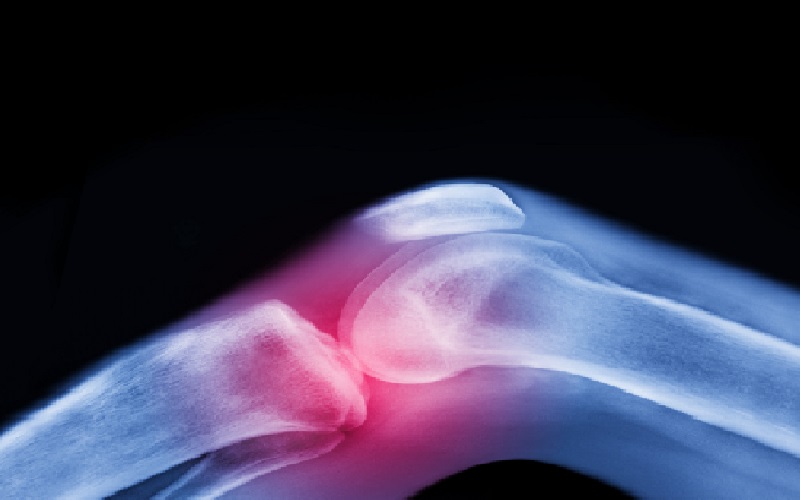

نيسان ـ تعتبر آلام المفاصل وتيبّس الركبتين وأوجاع الوركين من الشكاوى الشائعة بين كبار السن، وغالبا ما يُقبل بها كجزء طبيعي من أعراض الشيخوخة.

لكن الواقع الطبي يوضح أن هذا ليس مصيرا حتميا، فالفصال العظمي — أكثر أمراض المفاصل شيوعا في العالم — يمكن الوقاية منه وعلاجه بطرق غير دوائية فعّالة للغاية.

ويرى الخبراء أن أفضل علاج للفصال العظمي لا يوجد في علب الأدوية أو غرف العمليات، بل في الحركة المنتظمة والتمارين الرياضية. ومع ذلك، تظهر الدراسات أن القليل فقط من المرضى يتلقون الإرشاد المناسب لاستخدام هذا العلاج الفعال.

وتشير أبحاث أُجريت في أنظمة الرعاية الصحية في إيرلندا والمملكة المتحدة والنرويج والولايات المتحدة إلى نمط مقلق: أقل من نصف المصابين بالفصال العظمي يُحالون إلى العلاج الطبيعي أو التمارين الرياضية من قبل أطباء الرعاية الأولية. وفي الوقت نفسه، يحصل أكثر من 60% من هؤلاء المرضى على علاجات لا تتوافق مع الإرشادات الطبية، بينما يُحال نحو 40% إلى الجراحة قبل تجربة الخيارات غير الجراحية.